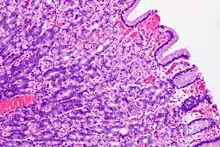

الوهدات المعدية تظهر واضحة كتعرجات في هذا المقطع من الغشاء المخاطي للمعدة. النسيج بصبغة الهيماتوكسيلين والإيوسين.

الوهدات المعدية هي فجوات ضيقة توجد في بطانة المعدة تكونها الطبقة المخاطية من المعدة، وتعد مداخل تؤدي إلى الغدد المعدية.[1] في المعدة البشرية يوجد الملايين من الوهدات المعدية التي ترقّط سطح بطانة المعدة، والتي تقع الغدد المعدية في عمقها. وتكون أعمق في منطقة البواب من باقي المناطق في المعدة.